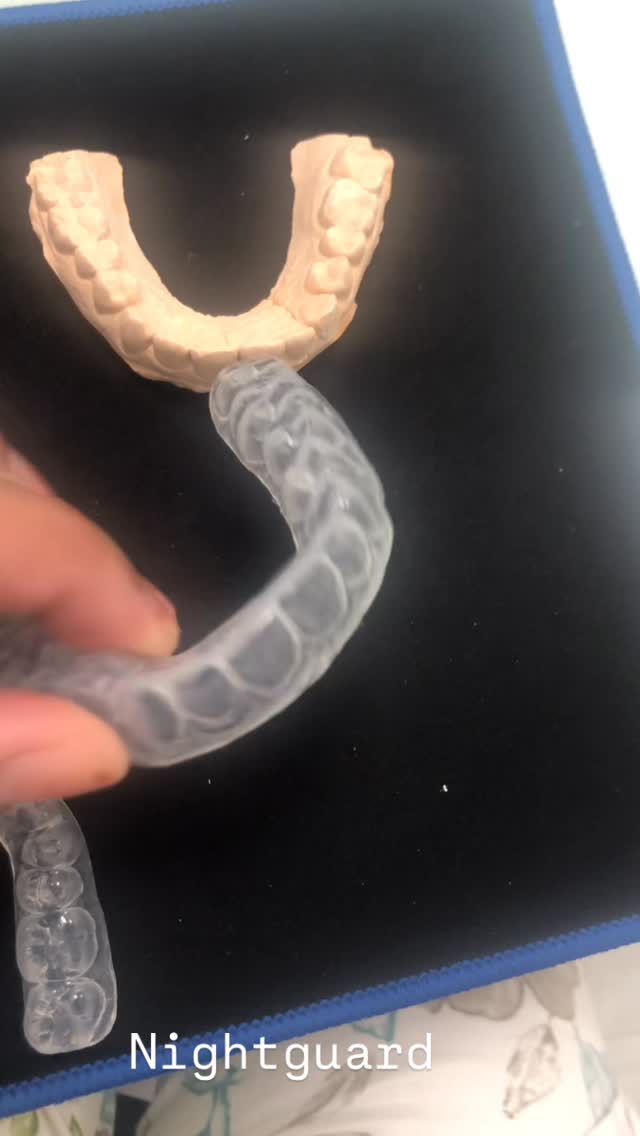

Explore Our Clinical Dental Gallery

Welcome to our official treatment gallery, showcasing the real results, smile transformations, and advanced dental care delivered by Dr. Madhuri. We believe that a picture is worth a thousand words when it comes to the art and precision of modern dentistry. Review our comprehensive visual portfolio below to see how our dedicated care helps patients achieve healthy, beautiful, and confident smiles.